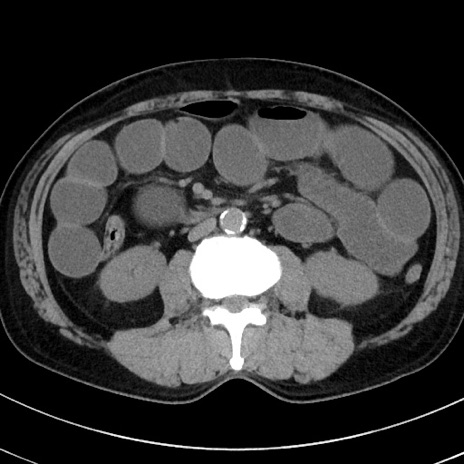

症例38(横断像)

【症例】70歳代 男性

【主訴】腹痛・嘔吐

【現病歴】昨晩より、嘔吐・腹痛あり。今朝になっても嘔吐あり。来院。

【既往歴】心臓バイパス手術、開腹胆摘、腸閉塞

【身体所見】BP 107/71mmHg、HR 116/min、腹部:平坦、軟、下腹部に軽度圧痛あり。反跳痛なし。

【データ】WBC 15100、CRP 0.32